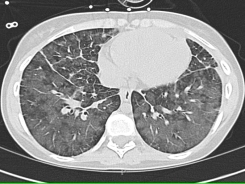

Figure 1: Chest CT. On parenchymal windows, the CT of the chest demonstrates diffuse bilateral patchy infiltrates in an alveolar pattern, as well as interlobular septal thickening. There is no pleural effusion noted.